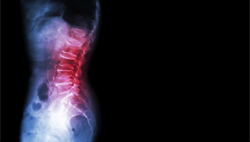

![xray]() Diagnosis

If Spondylolisthesis is suspected, a physician will examine X-rays of the back, looking for signs of vertebral fractures or if any have slipped out of place. An MRI or CT scan may also be used to pinpoint the site of the injury and to help inform treatment.